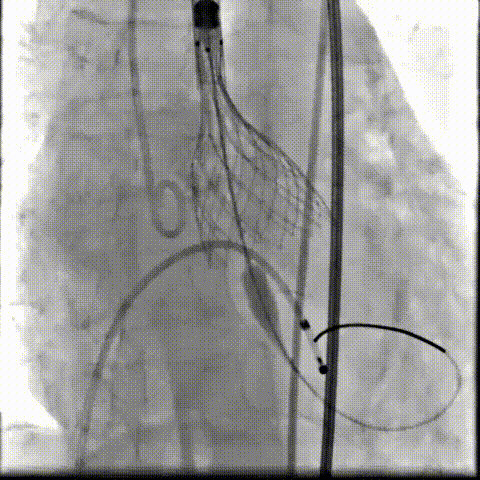

瓣膜工作位释放“烟囱支架”;

瓣膜(AV23)完全释放后,“烟囱支架”后扩

最终造影,“烟囱支架”显影清晰,瓣膜形态及LCA灌注良好

超声影像

TEE影像,烟囱支架显影清晰,支架内血流通畅